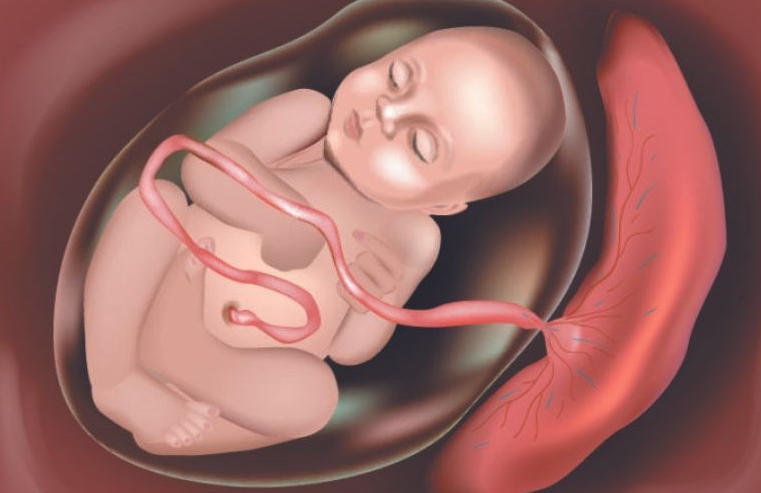

Rau cài răng lược xảy ra khi bánh rau xâm lấn vào thành tử cung sau khi sinh và không thể tách rời ra khỏi thành tử cung, dẫn đến tình trạng băng huyết sau sinh, rối loạn đông máu, thậm chí ảnh hưởng tính mạng của người mẹ.

Rau cài răng lược hay nhau cài răng lược là một hiện tượng bệnh lý xảy ra sau khi mẹ sinh em bé. Đây là tình trạng rau thai không bóc tách ra được khỏi thành tử cung do chúng bám chặt vào các cơ rồi xâm lấn đến các bộ phận xung quanh.

Khi rau thai bám vào thành tử cung quá chặt, không thể tự tách rời ra khỏi tử cung hoặc chỉ bong tróc một mảng nhỏ, các mạch máu sẽ bị mở ra và không được co lại, gây tình trạng băng huyết sau sinh và rối loạn đông máu sau sinh. Nếu không được xử trí kịp thời, mẹ có thể tử vong.